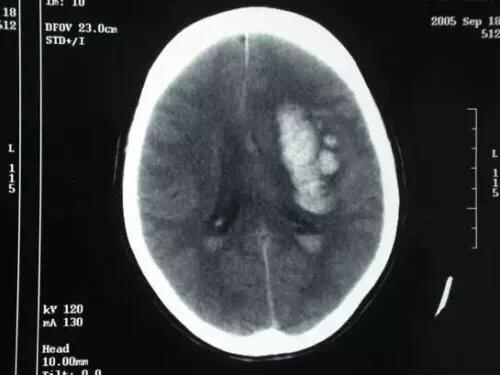

脑出血脑出血是由于血管破裂引起颅内压升高、远端脑组织供血中断的疾病,症状轻重要看出血程度和位置,一般留有后遗症,急性期病死率约在40%左右。除开一部分先天血管畸形、动脉瘤的患者可无诱因的发病外,脑出血最常见的诱因就是高血压,所有特别提醒各位高血压患者,请控制好你们的血压,别老是搞得自己头疼脑胀,这样很危险。

同样的脑出血也是这种情况,如果他只是非常小的脑出血,并不会严重影响生命,但是有的一些患者也可能会大量的脑出血,面积很大,从而造成了脑疝而引起患者非常严重的症状,甚至是死亡。